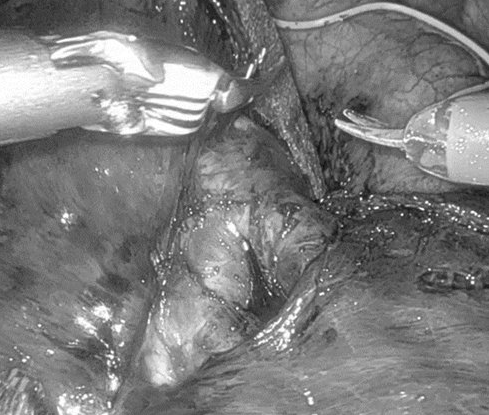

右圖:鍾秉儒醫師透過達文西機器人手臂輔助進行肺癌病人肺葉切除術。(鍾秉儒醫師提供)

鍾秉儒醫師指出,達文西手術系統的影像穩定、立體、且能將局部細節放大,加上仿真手腕的手術器械,能使外科醫師進行更精確的切除、修復和縫合等外科步驟。如此在進行達文西手術時,更能保留重要的組織,減少手術過程中不必要的神經、血管傷害。在有淋巴結轉移或腫瘤位置較深、不好切除的情況下,透過達文西手術,外科醫師能進行以往胸腔鏡手術無法完成的操作,更細緻地分離要切除的組織。

鍾秉儒醫師指出,衛生福利部健保署自2023年3月起新增多項達文西手術給付,病人可減輕一大部分醫療費用;這位病人為肺腺癌症第二期,雖沒有淋巴轉移,但手術後復發率仍可高達3到4成,選擇達文西手術,可做更多淋巴廓清,一些文獻指出,可有效降低復發率。病人術後第一天移除引流管,第二天出院,目前口服抗腫瘤藥物,並定期門診追蹤,日常生活一切正常,跟手術前一樣。